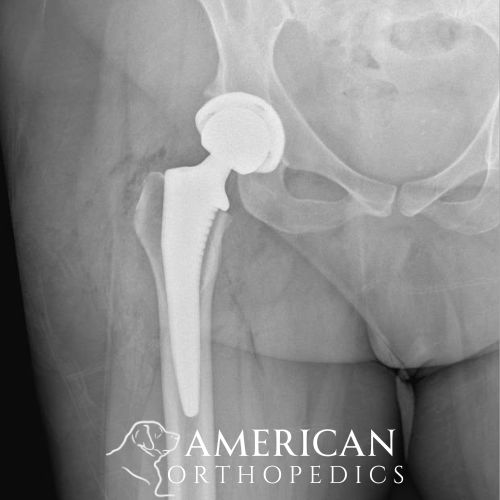

Anterior Hip Replacement for Osteoarthritis

Patient of Dr. Ratner.

Before

Anterior Hip Replacement for Osteoarthritis before - Drew Ratner MD Orthopedic Surgeon 1

After

Anterior Hip Replacement for Osteoarthritis Arthropathy after - Drew Ratner MD Orthopedic Surgeon 1